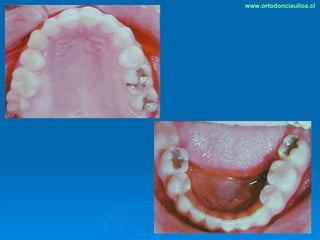

Este documento presenta dos casos clínicos de pacientes que recibieron tratamiento de ortodoncia. El primer caso fue de una paciente femenina de 14 años con apiñamiento dental y mordida cruzada que fue tratada mediante extracción de premolares y alineamiento dental. El segundo caso fue de un paciente masculino de 14 años con clase II esqueletal y desarmonía dentomaxilar que fue tratado con extracción de premolares y corrección de mordida. Ambos casos mostraron mejoría después de 3 años de tratamiento.